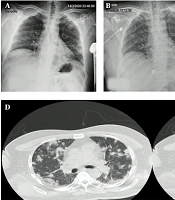

Case Report

Post-COVID-19 Massive Hemoptysis and Gastrointestinal Bleeding: A Case Report

Gholamreza SoleimaniORCID*,

Saeedeh YaghoubiORCID,

Elham Shafighi ShahriORCID